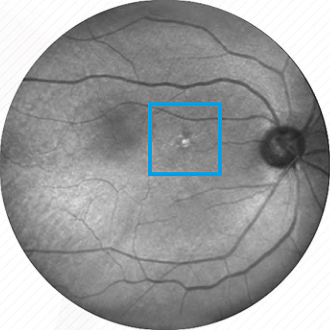

Altersbedingte Makuladegeneration (AMD)

Ablagerungen in der Netzhaut führen zu einem zunehmenden Verlust der Sehkraft vor allem im zentralen Sichtfeld. Nur eine frühe Therapie kann die AMD bremsen.